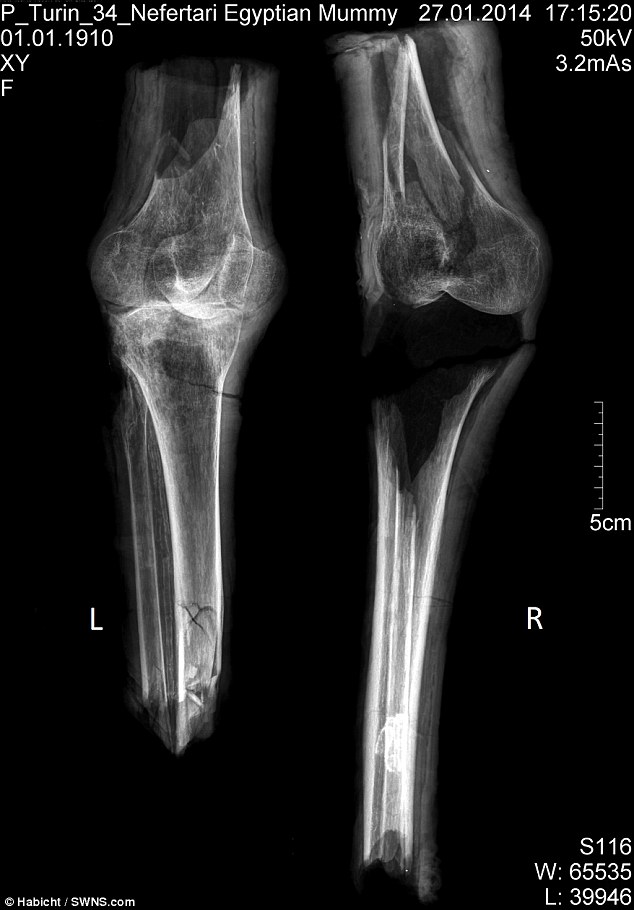

In examining the mummified remains, the team carried out a number of tests.

Firstly, they used X-rays to image the bones beneath the fragile wraps, confirming the samples as human knees.

They then compared structures with knee samples from ancient Italy and of modern Cape Coloured females.